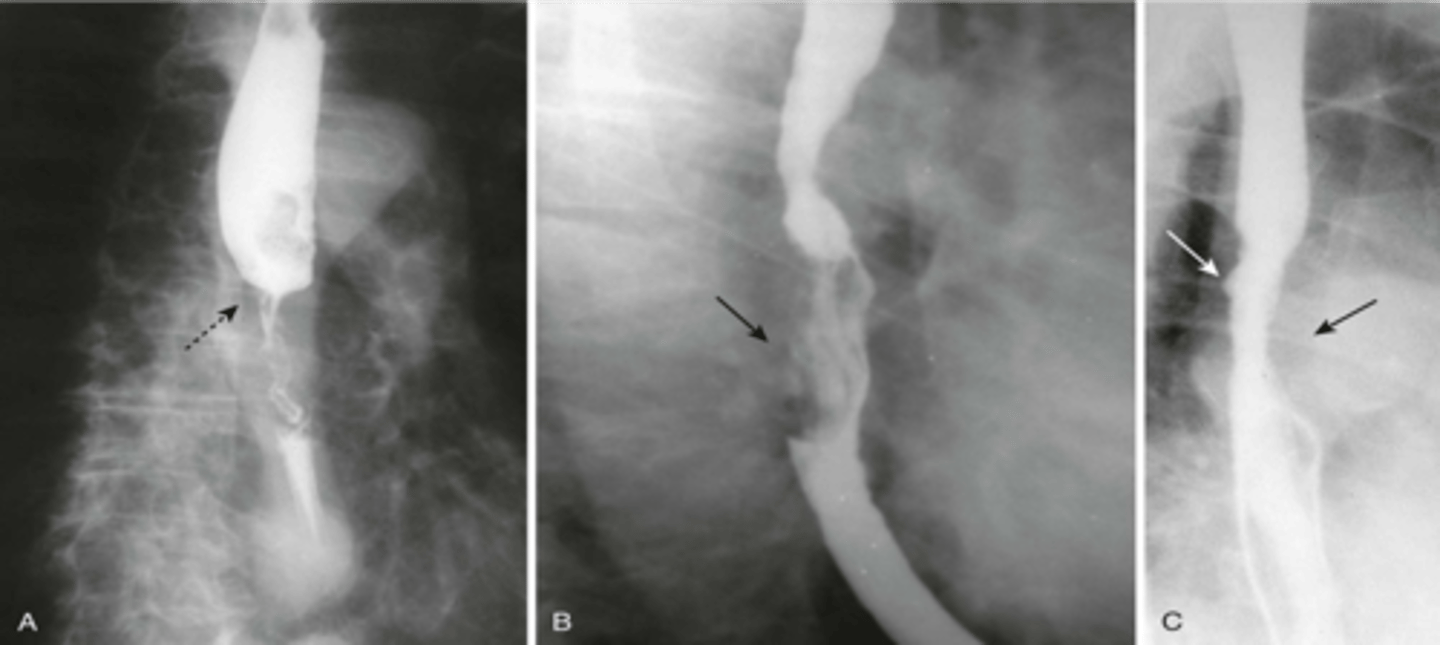

A: annular constriction

B: Polypoid mass

C: rigid wall and ulcer

Esophageal cancer: ulcers and mass